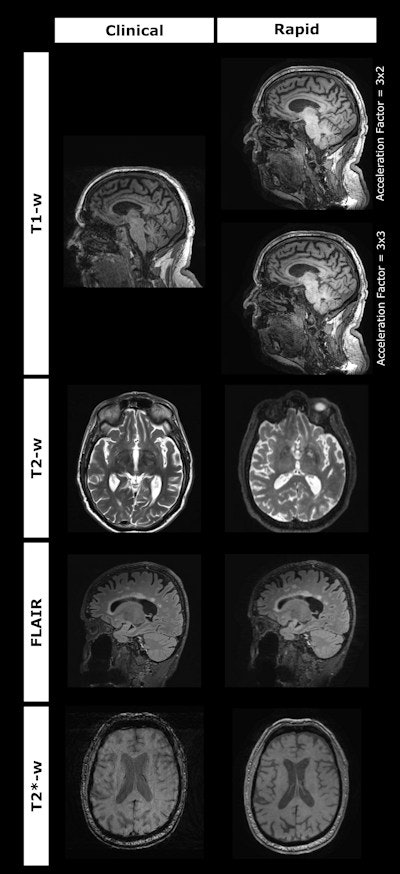

Examples of scans acquired from the clinical and rapid protocols for each sequence. Image and caption courtesy of Haroon Chughtai, PhD.MRI for diagnosing dementia does have some limits, most notably image degradation that can affect the clinical usefulness of its images, according to Chughtai. To address this limitation, his group developed a prototype ultrafast MRI protocol based on a technique called wave-controlled aliasing in parallel imaging, or CAIPI, which is designed to speed 3D exams.

The standard protocol consisted of T1w, T2w, FLAIR and T2*/SWI sequences, while the rapid protocol used Siemens' work-in-progress wave-CAIPI sequences (3D MPRAGE, 3D FLAIR, 3D T2 and 3D T2*).